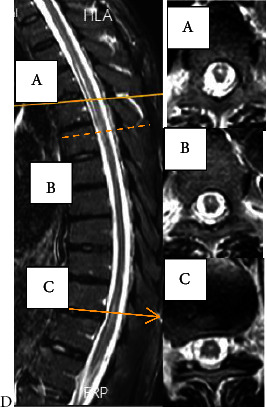

Introduction: Longitudinal extensive transverse myelitis (LETM) has four main causes: inflammatory, malnutrition, vascular, and infectious causes. Among the commonly described viral causes leading to LETM are the Herpesviridae family, HIV, and HTLV-1. Case Presentation. A 43-year-old man presented with asymmetric weakness of the lower limbs (the left side was weaker), urinary retention, and flank pain. The symptoms began five days after shingle eruption and progressed over twelve days. He was diagnosed with longitudinal extensive transvers myelitis extending from T4 to T6, which corresponded to the same dermatome involved in shingles. The PCR result of cerebrospinal fluid was positive for varicella-zoster virus with a viral load of 500 copies/ml. Additionally, the initial HIV enzyme-linked immunosorbent assay (ELISA) test was positive, and his CD4 count was 72 cells/mm3. Other lab results were normal. Based on the appearance of LETM in the thoracic MRI at T4-T6, VZV myelitis was diagnosed, and treatment was initiated with acyclovir (30 mg/kg divided daily for twenty-one days), methylprednisolone (1 g/day for three days), prophylactic antibiotics (trimethoprim/sulfamethoxazole, rifampin, and isoniazid), and antiretroviral therapy (dolutegravir and Truvada). After 2-month follow-up, he was nearly free of symptoms.